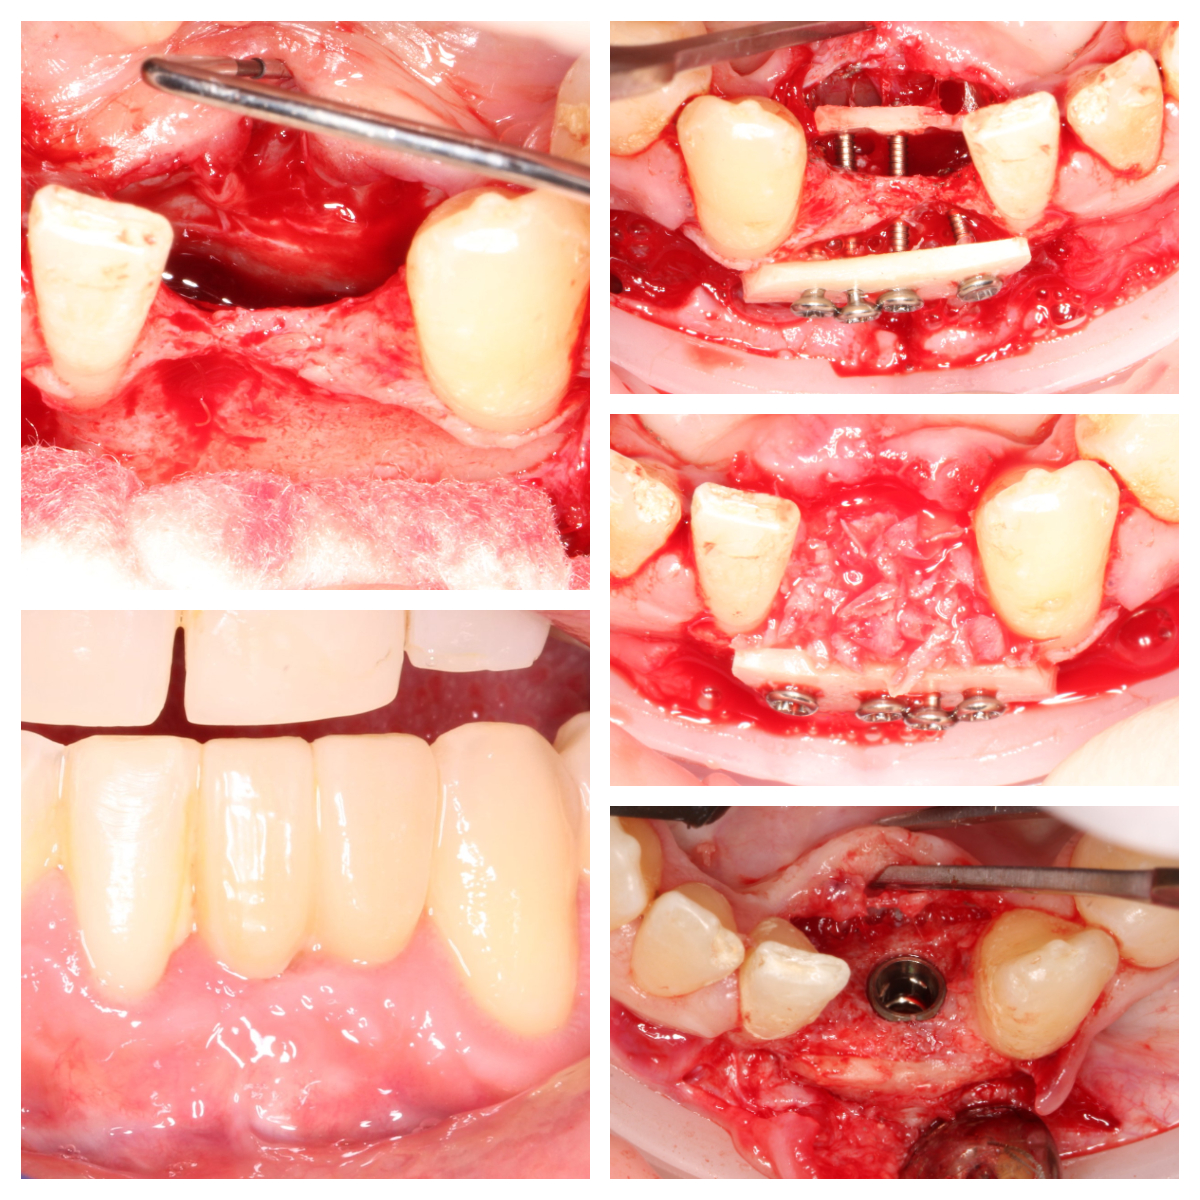

“Beyond Repair: Transformative Bone Grafting and Implant Therapy for Devastating Anterior Teeth Loss”

Dr Noroozi IMPrESS Perio Implant Center Bone Grafting for Dental Implants Khoury Technique